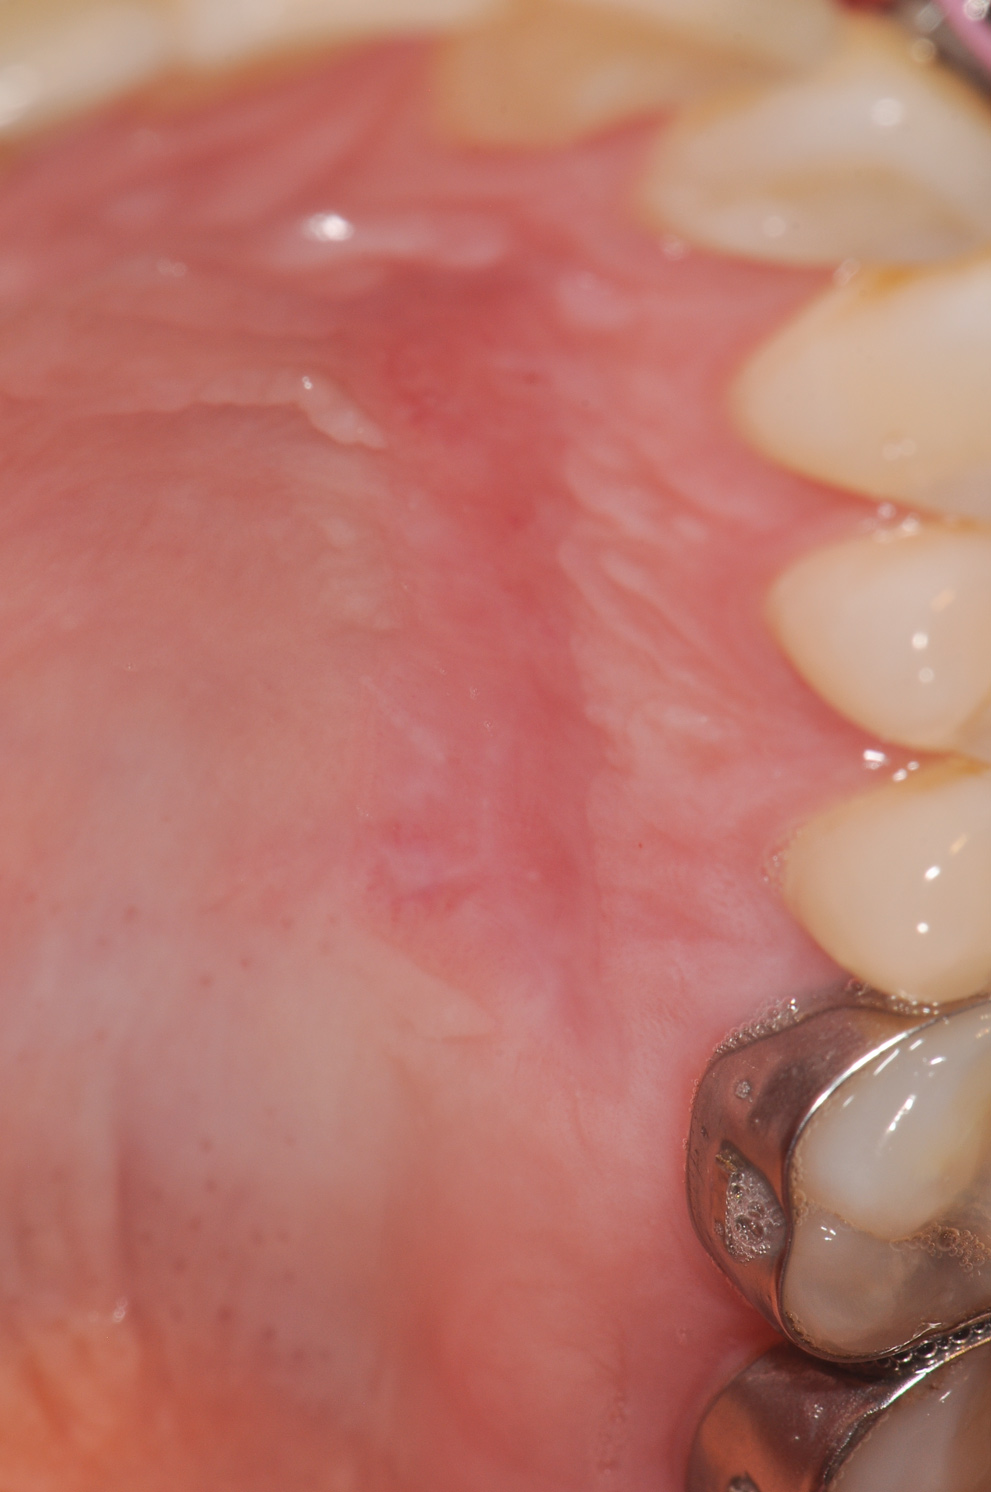

Regarding furcation defects, based on the available evidence, the AAP workshop concluded that regenerative therapy is a viable option to achieve predictable outcomes for their treatment in certain clinical scenarios.13 Periodontal regeneration has been established as a viable therapeutic option for the treatment of various furcation defects, including Class II defects, which represent a highly predictable scenario. The application of combined therapeutic approaches (ie, barrier, bone replacement graft with or without biologics) appears to offer an advantage over monotherapeutic algorithms.13 Figure 12 through Figure 15 depict the periodontal regenerative treatment of two previously restored teeth with intrabony and furcation defects using mineralized FDBA and EMD.

(12.) Pretreatment photograph of two previously restored teeth exhibiting gingival recession and probing depths equal to or greater than 15 mm.

Figure 12

(13.) Pretreatment radiograph showing intrabony and furcation defects.

Figure 13

(14.) Intrasurgical photograph of regenerative treatment with mineralized FDBA and EMD.

Figure 14

(15.) Postoperative radiograph taken 6 months after treatment demonstrating 3- to 4-mm probing depths.

Figure 15